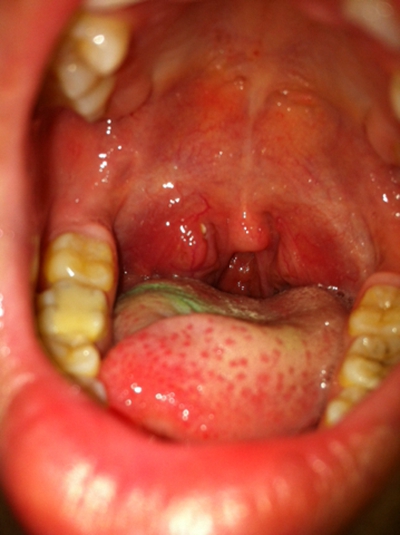

食道炎的症狀圖 (8)